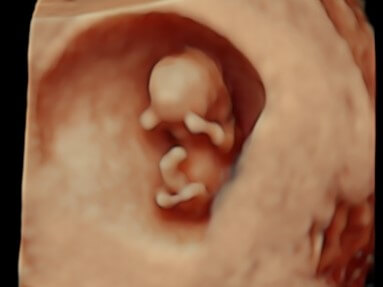

There are few things in this world as precious as the bond between mother and child. Love View was born from the joy of providing a unique prenatal bonding experience for expectant mothers and their family.

SEE OUR WORKWe are a locally owned and operated family business. Our supervising sonographer Samantha is a registered sonographer with the American Registry for Diagnostic Medical Sonography and has over 15 years of experience. She is the mother of four amazing children and loves the opportunity to talk to and support new moms. Our studio has a Board Certified Obstetrician who serves as our Medical Advisor. You can be sure you are in the best hands with Love View.

Pregnancy is an extraordinary time in a woman’s life, we consider it a genuine honor to provide this unique experience to expectant mothers, their family and friends. We look forward to your session. We can’t wait to meet the newest member of your family!